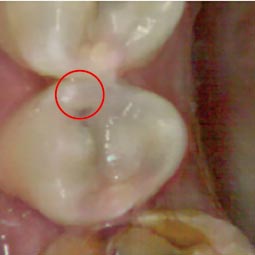

そんな誰もが経験したであろうむし歯ですが、そんな中でも気をつけたいのが「見えないむし歯」です。写真1のように何ともなさそうな歯の方が、ある日激痛を覚えてご来院されるというのは、珍しくないことなのです。実際歯科でレントゲンを取り、蓋を開けてみれば写真2のように歯の内部でむし歯が進行してしまっています。

これらは、歯の見えにくい部位から出来たむし歯が内側に進行したり、治療をした歯の詰め物の隙間から入ったむし歯が、修復物の進行したりすることで起こり得る症状です。見た目は通常の健康な歯とほぼ変わらないので、自発痛(お痛みがでる状態)が出てこない限りこの虫歯に気づくことはありません。あるいは学校や会社の歯科検診であっても、レントゲンを取らない検診では気づかないことも十分にあり得ます。